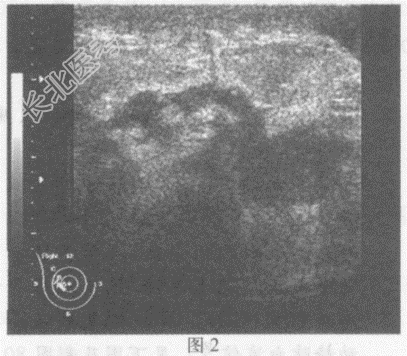

超声综合描述: 右乳腺腺体层厚度2.8cm,明显增厚, 结构紊乱,内回声明显不均, 乳头外侧及外下象限可见数个大小不等,形态不规则极低近似无回声区(图1、图2、图3), 部分呈树枝状分布,探头加压后局部压痛明显; 右乳头外上象限可见形态不规则片状低回声(图4),CDFI: 右乳腺腺体层内血流信号较左侧丰富。